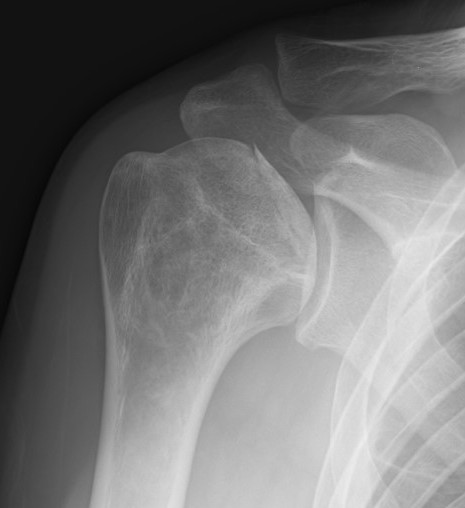

DDx

Chondroblastoma / Chondrosarcoma

Enchondroma

Bone island